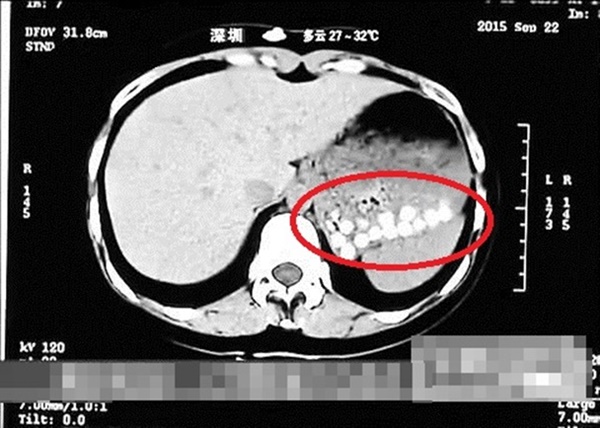

กลายเป็นข่าวฮือฮาที่สร้างความตื่นตกใจให้กับชาวเน็ตไม่ใช่น้อย เมื่อสื่อท้องถิ่นของจีนได้มีรายงานอ้างว่า พบชานมไข่มุกปลอม ที่คาดว่าทำมาจากยางรถยนต์เก่าและหนังทำรองเท้า ซึ่งเรื่องดังกล่าวได้ถูกเปิดเผยเมื่อนักข่าวรายหนึ่งทานชานมไข่มุกเข้าไปแล้วป่วย และผลจากการซีทีแสกนพบว่าเม็ดไข่มุกที่กินเข้าไป ยังมีสภาพเป็นเม็ด ๆ ไม่ยอมย่อย ตามที่ได้เสนอข่าวไปแล้วนั้น [อ่าน งานปลอมมาอีกแล้ว ! พบชานมไข่มุกปลอมที่จีน ทำจากยางรถ-หนังรองเท้า]

- ทดลองกิน แล้วครึ่งชั่วโมงไปซีทีแสกน เห็นเป็นเม็ด ๆ (ดูรูป) ... แสดงว่าตั้งใจกลืน ไม่ได้เคี้ยวเลย กลืนเสร็จไปหาหมอ

ภาพจาก เฟซบุ๊ก Jessada Denduangboripant, hongkongfp via Shandong TV